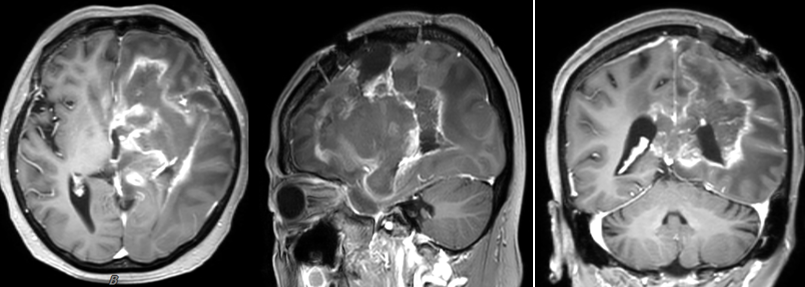

图片

图注:左侧额顶叶胶质瘤术后,术区及周围示不规则团片状稍长、稍短T1长、等及稍长、稍短T2信号改变,增强扫描呈局部片絮状强化、局部边缘不规则强化、局部强化不著,病变跨中线部位、下达脑干、左侧小脑中脚,左侧脑室受压略变窄,中线结构稍右移。上述表现较前有好转。